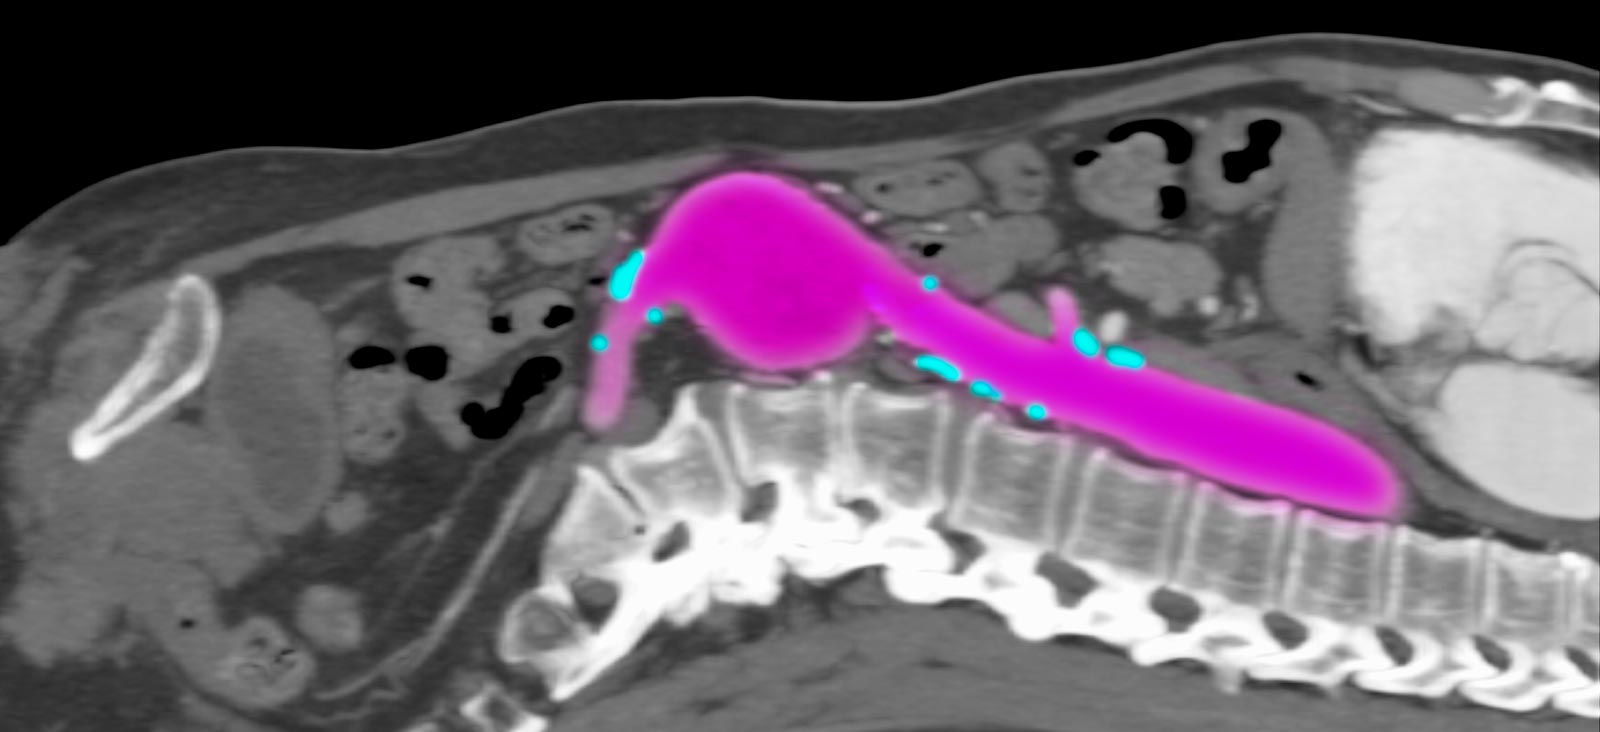

At UT Southwestern, our vascular specialists use computed tomography angiogram (CTA) scans to show detailed images of our patients’ arteries. They use these scans to choose the best treatment approach. Our specialists review patients’ comprehensive medical data to evaluate how an endovascular stent procedure compares with traditional surgical options or determine if a combined approach is needed.

Depending on the patient’s overall health and specific condition, our specialists will recommend the appropriate procedure. UT Southwestern’s Advanced Endovascular Aortic Program focuses on treating complex aortic diseases using total endovascular therapies that are minimally invasive. Led by Carlos Timaran, M.D., the team has developed a Physician-Sponsored Investigational Device Exemption (PS-IDE) protocol, which we have used since 2014 to implant fenestrated and/or branched stent-grafts.

With these devices, our vascular surgeons can repair most aortic diseases, such as complex suprarenal (above the kidneys) and thoracoabdominal aortic aneurysms and chronic dissections, using this minimally invasive approach. Our endovascular aortic approach is appropriate for most patients, even those who cannot have open surgery, providing a faster recovery.